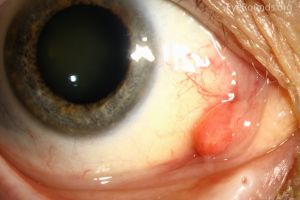

Pyogenic granuloma (PG) is a common, non-cancerous growth of blood vessels, first identified by Poncet and Dor in 1897 as "botryomycosis hominis."It is also known as lobular capillary hemangioma, granuloma pyogenicum, and granuloma telangiectaticum.[1] [2][3] The term "lobular capillary hemangioma" is more accurate, as these growths do not produce pus or involve the chronic inflammation typical of granulomas. PG can appear anywhere on the body, most frequently on the skin, affecting men and women equally. However, they are twice as common in the mucous membranes of women, such as the conjunctiva and gingiva, and are often associated with pregnancy.[4] These growths appear as smooth, red-purple bumps, either flat or on a stalk, and can recur after removal. They are also linked to inflammation following strabismus surgery[5] or other eye conditions like styes and chalazia.

- Patients will present with a rapidly growing, painless, red polypoid papule or nodule with an average size of 6.5mm,[17] reaching its maximum in a few weeks

- In the ocular region, they may arise on the lids, conjunctiva, and rarely the cornea along wound sites either after trauma or post-operatively